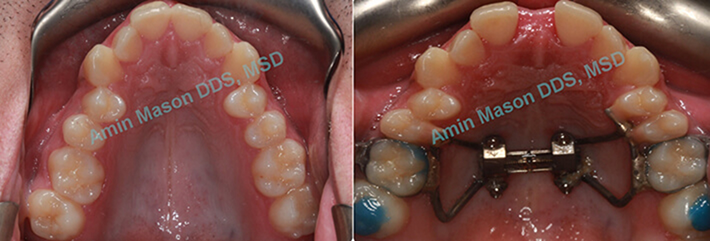

TADs Used to Open Maxillary Suture in Older Patients

Adults patients presented with narrow maxilla and crossbite. TAD-supported expanders were used to open the maxillary suture instead of surgical procedure.